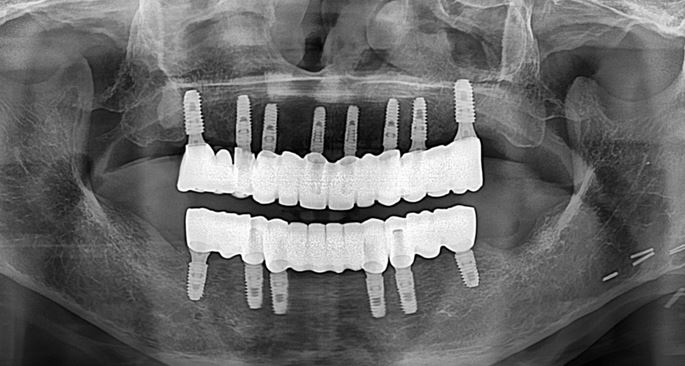

전체 보철물 세팅

6개월 정도 지난 후 임플란트 보철 세팅

보철이 없는 동안은 임시 의치(틀니)를 사용함

앞니의 경우 잇몸이 내려가서 치아 길이가 길어보일 수 있기 때문에 보철 부분에 잇몸 색상을 넣어서 자연스럽게 하였습니다.